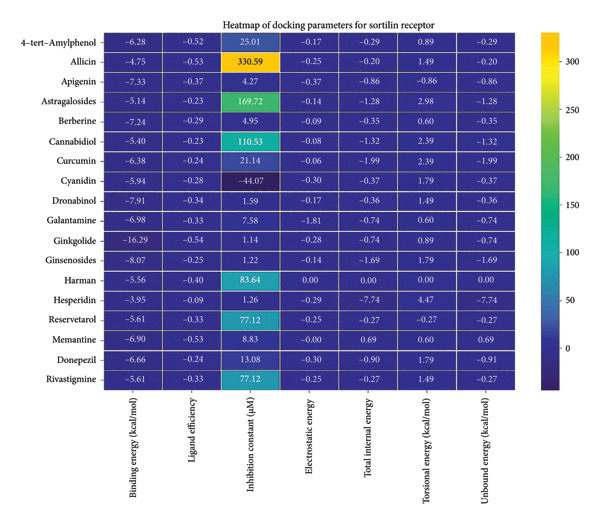

3.2. AutoDock Vina Results: Sortilin Receptor

The sortilin receptor demonstrated the highest affinity for ginkgolide (−16.29 kcal/mol), representing the strongest binding observed across all targets. Key interactions for ginkgolide involved hydrogen bonding with ARG292 and TYR318. Other strong binders included ginsenosides (−8.07 kcal/mol) interacting with ILE141 and MET139 and dronabinol (−7.91 kcal/mol); for instance, 4‐tert‐amylphenol formed highly favorable bonds with ARG292 (donor–acceptor D–A distance: 2.92, angle Ǻ and 3.11 Ǻ:164.68°, Figure 2 details the binding characteristics of all tested ligands. Table 2 shows the predicted hydrogen bond interactions for selected molecules and drugs against sortilin, clusterin, amyloid, and tau proteins.

The heatmap in Figure 6 provides a comprehensive visual interpretation of the AutoDock Vina docking analysis of natural ligands (light blue‐coded) and reference drugs (orange‐coded) against four key AD‐related receptors. Ginkgolide consistently demonstrates strong (deep red coloration) binding energies across all four receptors: sortilin (blue‐coded), clusterin (green‐coded), Aβ peptide (yellow‐coded), and tau proteins (purple‐coded). Natural ligands exhibited varied yet significant binding profiles; ginsenosides showed strong affinities for tau proteins and Aβ peptide, with moderate binding to sortilin and clusterin. Dronabinol displayed particularly strong interactions with sortilin and Aβ peptide, while berberine and apigenin consistently showed favorable binding across multiple targets, underscoring their broad spectrum of action. In stark contrast, hesperidin consistently presented among the weakest binding affinities across most receptors (indicated by blue/lighter colors), suggesting limited direct molecular interaction.

Comparative analysis against the established reference drugs—memantine, donepezil, and rivastigmine—revealed that several natural compounds, most notably ginkgolide, achieved binding affinities that were superior to these therapeutic agents across various AD‐related targets, highlighting their significant potential as alternatives or adjuncts. The hierarchical clustering patterns displayed by the dendrograms provided further insights: Molecules grouped together along the y‐axis (ligand–receptor pairs) often shared similar overall binding characteristics. For example, ginkgolide consistently clustered within highly favorable binding groups across multiple receptors (Figure 7), and groups like ginsenosides and cyanidin showed similar strong binding patterns toward tau proteins. Notably, certain natural ligands, such as allicin and harman, clustered with other smaller, more drug‐like natural compounds. Importantly, this clustering also revealed instances where natural ligands exhibited similar binding profiles to reference drugs like memantine, donepezil, or rivastigmine, suggesting potentially shared binding modes or therapeutic mechanisms.